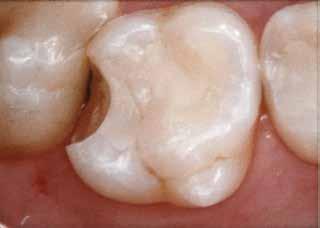

En dybtliggende amalgam-misfarvning udgør en af de mest vanskelige udfordringer ved udskiftning af restaureringer. Transcend Universal Body farven blev anvendt til at erstatte amalgamen, uden brug af blokeringsmateriale. Bemærk, hvor fremragende farven blender ind i den bevarede crista obliqua.

Før Efter